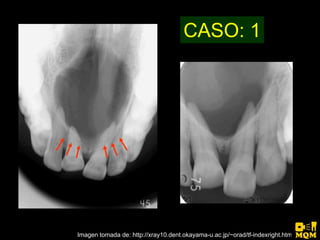

El quiste nasopalatino es un quiste embrionario situado en la línea media en la parte anterior del paladar, que se origina de los restos del conducto nasopalatino. Generalmente aparece entre los 40-60 años y se presenta como un aumento de volumen blando y no doloroso entre los incisivos centrales superiores que puede causar divergencia radicular. Las características radiográficas incluyen una lesión radiolúcida, bien delimitada y de forma redondeada u ovalada que cruza la línea media maxilar.